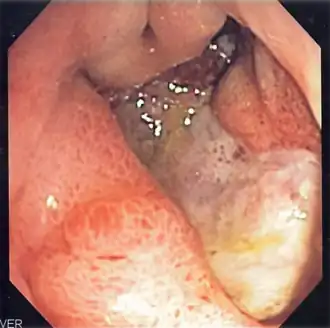

| Úlcera gástrica profunda | |